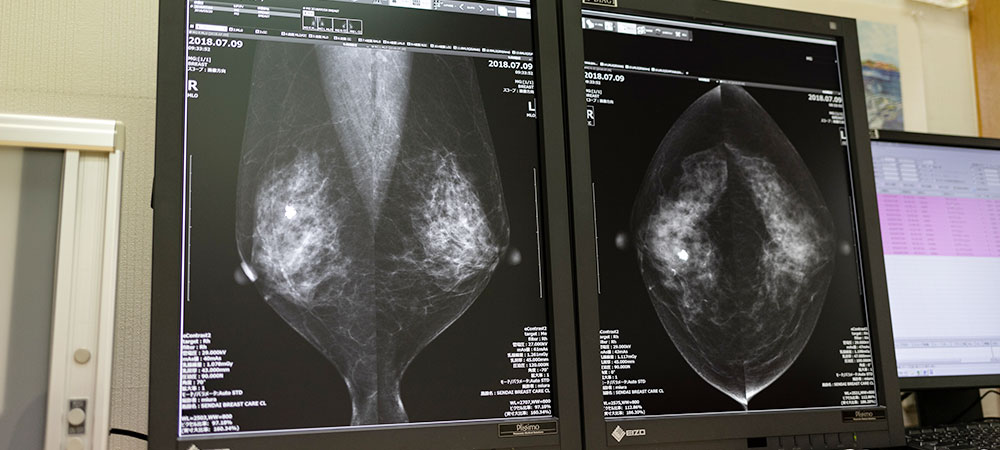

乳がんの精密検査

乳がんの精密検査について

検診でしこりが見つかった場合、「穿刺吸引細胞診」か「針生検(組織診)」で乳がんの確定診断を行います。